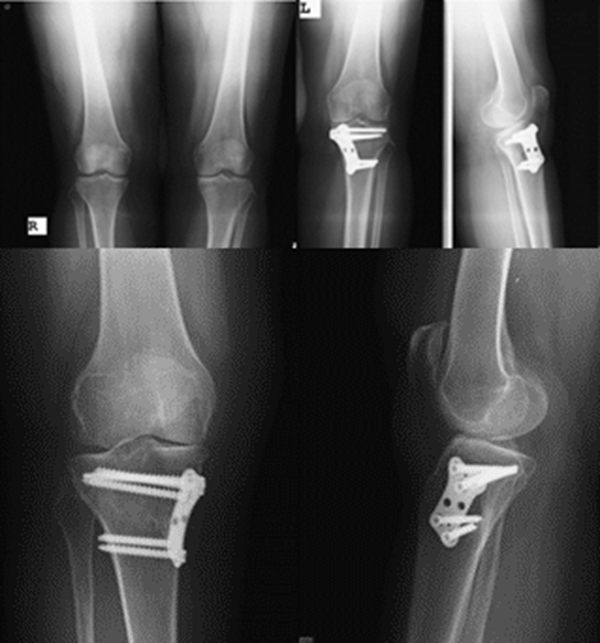

两种截骨对比 OWHTO VS CWHTO

OWHTO和CWHTO同样可获得良好临床疗效。但CWHTO存在腓总神经损伤的风险。

病例1:46岁,滑雪运动员,多发韧带伤,内翻畸形膝关节疼痛,开式截骨后二月全负重行走,膝关节疼痛缓解

病例2:男性,19岁,因发现右膝关节内翻、过伸畸形伴跛行5年(左侧膝关节也有类似畸形,暂时无症状)。于2006年7月就诊,其母亲也有类似病史。查体:右膝关节内翻畸形约15度,应力下过伸约20度,内翻及外翻时膝关节均有松动感,Lanchman试验(+)。无负重下X片示:右膝关节内翻畸形约15度,胫骨平台无后倾,倒呈前倾13º。膝关节MR示:右膝内侧股骨及胫骨软骨面已有缺损并囊性变。诊断:先天性膝关节内翻畸形(Blount病)。

术前X线可见右膝关节内翻畸形约15°,胫骨平台前倾畸形13°

术后6月X片示右膝内翻、前倾畸形已矫正,胫骨截骨处愈合,腓骨未愈合,但无症状。

胫骨高位截骨术(OWHTO和CWHTO)通过截骨,改变下肢力线,延缓关节炎进展,适用于治疗伴有内翻畸形的膝关节内侧间室骨关节炎,两者截骨术式均可获得良好临床疗效。

CWHTO不需植骨,但矫正有限,需行腓骨截骨,容易损伤腓总神经,造成肢体短缩;

OWHTO不需腓骨截骨,不伤腓总神经,可早期功能锻炼,但骨缝大时往往需行植骨,不愈合率相对CWHTO高;